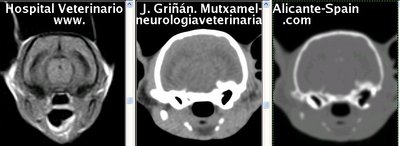

Se muestran cortes transversales de Resonancia Magnética (imagen a la izqda del lector), TC contrastado para tejidos blandos (imagen del centro) y TC contrastado para tejidos duros (imagen de la derecha del lector).

Nótese como la Resonancia supera al TC en el contraste de tejidos blandos (encéfalo y médula espinal) y en el de líquidos (ojo y líquido cefalorraquídeo), mientras que el TC supera a la resonancia en el contraste de tejidos duros (hueso) y aire (senos, cavidad nasal y bullas)

Cortes a nivel de los lóbulos cerebrales parietales